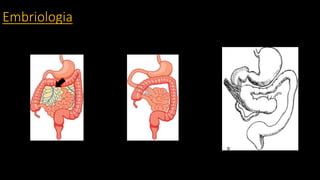

Embriologia